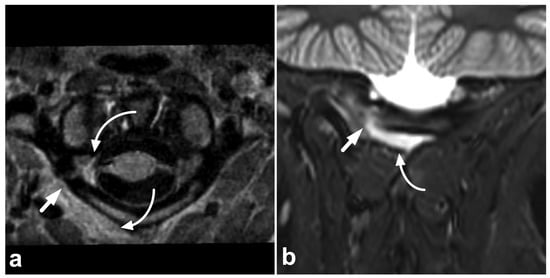

Figure 6.

(a) Axial PD-weighted. (b) Coronal STIR. (c) Sagittal T2-weighted. (d) Sagittal T1-weighted, off-midline. A 14-year-old female, motor vehicle accident. Non-displaced right-sided fracture at the posterior arch of the C1 is marked with straight arrows. The fracture line extends to the transverse foramen, but the vertebral artery (arrowhead) is intact, with a normal flow void and no intramural hematoma. There is a hemorrhage (curved arrows) around the fracture inside and outside the transverse foramen.